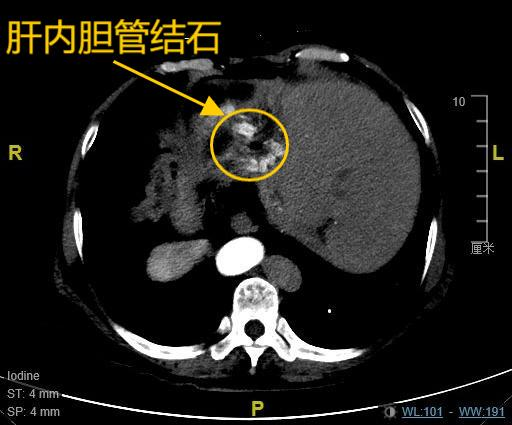

患者韩女士(化名),67岁,8年前因胆总管结石、胆囊结石曾接受传统开腹手术,术后三年结石复发,导致其长期饱受肝内胆管结石困扰,反复发作的右上腹疼痛严重影响了她的生活质量。更为特殊的是,韩女士存在罕见的全内脏反位,即医学上所指的“镜面人”,她的心脏、肝脏、脾脏等脏器均与正常解剖位置呈镜像反位分布,这是一种罕见的内脏解剖变异,发生概率约万分之一,这为手术操作带来极大挑战。8年前,由于特殊的身体情况,其开腹手术曾耗时长达10小时。近期复查的肝胆CT提示:肝内胆管多发结石伴肝左叶萎缩,肝总管及部分二级胆管扩张。面对多家医院“需再次开腹”的诊疗建议,患者坚持寻求微创解决方案,最终慕名求诊于哈医大一院肝脏微创外科麻勇主任团队。

查阅相关影像学检查资料后,麻勇主任带领团队为其进行了多学科联合会诊,并确定了进一步治疗的方案。"这是典型的高危复杂病例!"麻勇主任分析指出,患者同时存在高龄、脑梗、2型糖尿病、冠心病、间质性肺炎及血小板减少等多重风险因素,传统开腹手术可能引发包括切口感染、切口疝以及多种心肺并发症,而微创手术则面临三大挑战:全内脏反位导致的解剖定位错乱,术中易发生方向误判;既往开腹手术造成腹腔粘连,胆道前次手术创面会导致分离异常困难;血小板减少带来的术中出血风险。通过三维重建技术精准评估患者腹腔情况后,团队最终确定达芬奇机器人辅助腹腔镜肝切除联合胆道镜取石手术为最优方案。